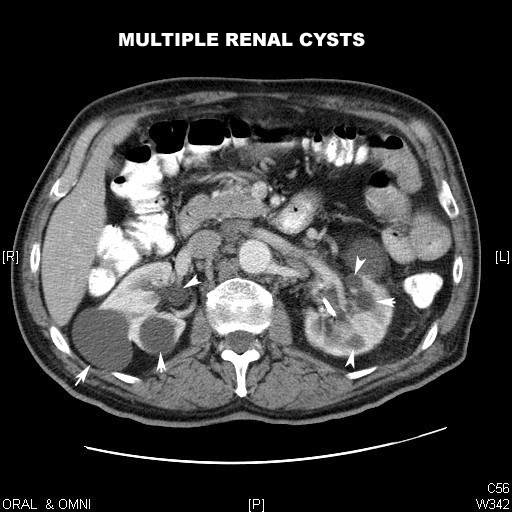

Contrast CT characteristics: